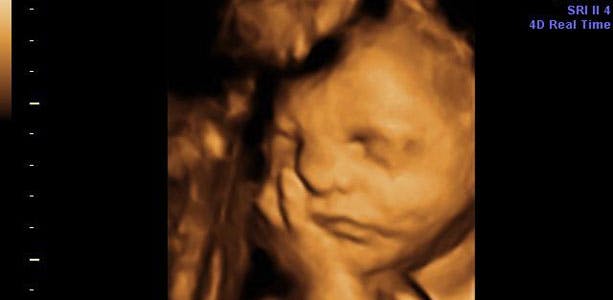

Gravid uge 32: Aktivitet i hjernen

Klitoris hos piger er stor og ikke dÊkket af skamlÊberne endnu - det sker fÞrst i de sidste uger af din graviditet. Der er aktivitet i hjernen, bÄde nÄr barnet sover og er vÄgent. NyfÞdte bÞrn husker, for eksempel et bestemt musikstykke eller en sang, hvis I spiller eller synger jÊvnligt. I slutningen af ugen mÄler barnet cirka 40 centimeter og vejer omkring 1900 gram. LÄrbenet mÄler cirka 6 centimeter, maveomkredsen cirka 28,5 centimeter og hovedet cirka 8,6 centimeter i diameter.